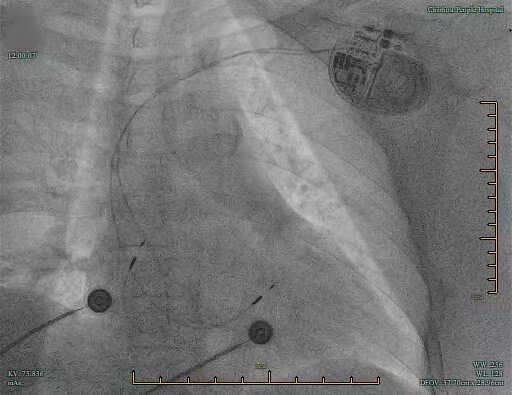

经过两天的精心调理和全面术前评估(排除感染、电解质紊乱等禁忌),4月19日中午,方中主任团队为患者实施永久性双腔起搏器植入术。与传统的右心房+右心室心尖部起搏不同,团队根据患者病情特点,制定了全生理性起搏方案:心房侧选择巴赫曼束起搏(Bachmann’s bundle pacing),通过将心房电极精准定位在房间传导束(巴赫曼束,或后上束)上,实现双心房同步激动,最大程度保留房室传导的生理顺序,降低房性心律失常及心衰风险;心室侧选择左束支区域起搏(left bundle branch pacing, LBBP),将心室电极经室间隔穿至左束支区域,直接夺获心脏传导系统,实现心室电-机械同步,避免传统右心室起搏导致的心室不同步、心肌重构和心功能恶化。

该患者为高度房室传导阻滞,未来需高比例心室起搏,若采用传统起搏方式,长期可致起搏器诱导性心肌病。而巴赫曼束+左束支联合起搏实现了真正的“全生理性起搏”——从心房到心室,沿自身传导系统下传,具有保留房室同步、预防心衰发生、降低房颤风险、起搏参数更优等明确获益。手术历时约2小时,过程顺利,术后起搏器程控显示:心房起搏夺获巴赫曼束,心室起搏QRS波宽度仅109ms(接近正常),起搏阈值理想。术中及术后患者无任何特殊不适。